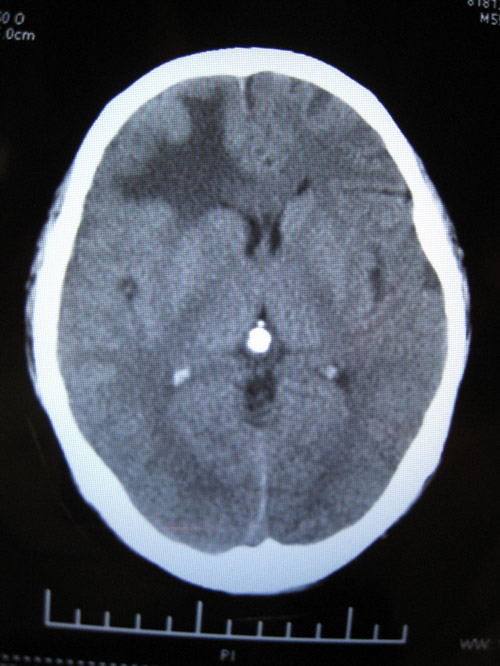

CTʱ¼ä2008-07-15 ÔçÉÏ9µãÖÓ

CT±¨¸æ

ÓÒ²à¶îÒ¶¼ûÇ·¹æÔòÍÅÆ¬ÉÔ¸ßÃܶÈÓ°£¬ÆäÖܱ߼ûƬ״µÍÃܶÈÓ°Ë®Ö×Ó°»·ÈÆ£¬±ß½çÇ·Ç壬¾Ö²¿¿É¼ûռλЧӦ£¬ÓÒ²à¶îò¨Ò¶ÄÔ¹µ±ädz£»ÓàÄÔʵÖÊÄÚδ¼ûÒì³£ÃܶÈÓ°£¬ÖÐÏßÏò×ó²àÒÆÎ»£¬Â¹Çδ¼ûÃ÷ÏÔ¹ÇÕÛ¡£

ÎÊÌâ²¹³ä£ºCTƬ2008-07-15 µÄÓ¡ÏóÊÇ£ºÓÒ²à¶îÒ¶ÄÔ´ìÁÑÉ˰éѪÖ×Ðγɣ¬¶ÔÕÕ08.07.09ƬѪÖ×ÉÔÎüÊÕ£¬Ë®Ö×Ïà·Â¡£

ѪÖ×ѹÆÈѪ¹ÜÉñ¾¡°ÖÐÏßÏò×ó²àÒÆÎ»¡±¡°Õ¼Î»Ð§Ó¦¡±